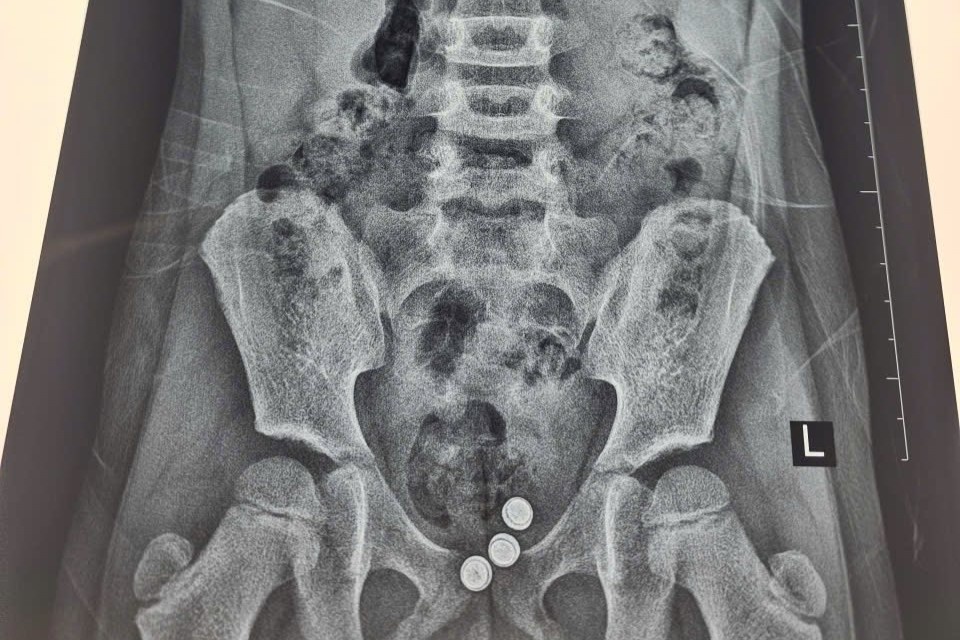

Bé gái quê ở Nam Định tuổi được đưa vào Bệnh viện Phụ sản Hà Nội khám trong tình trạng vùng kín viêm đỏ, chảy dịch và có mùi rất hôi.

Kết quả siêu âm ổ bụng và nội soi dạ dày, đại trực tràng của bé gái 8 tuổi không phát hiện bất thường. Tuy nhiên, bác sĩ nghi ngờ có dị vật trong đường âm đạo.

Các bác sĩ vừa can thiệp, lấy ra ba viên pin từ vùng kín một bé gái 5 tuổi. Dị vật đã gây viêm đỏ và tổn thương âm đạo của trẻ.